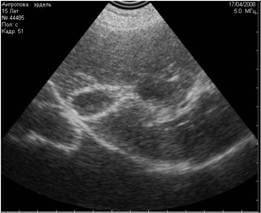

Рис. 16. На этой фотографии представлено два вида теней. Тень от лоханки является истинной тенью. Тень от кривизны капсулы поверхности является режущей. |